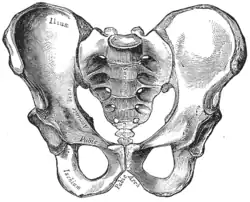

Imagem da pelve. | |

O sacro (plural: sacra ou sacrums)[1] é um osso grande e triangular localizado na base da coluna vertebral e na porção superior e posterior da cavidade pélvica, onde está inserido como uma fatia entre os dois ossos do quadril. Sua parte superior se conecta com a última vértebra lombar, e sua parte inferior com o osso da cauda ou cóccix (S1 a S5) entre 18 e 30 anos de idade.[2]